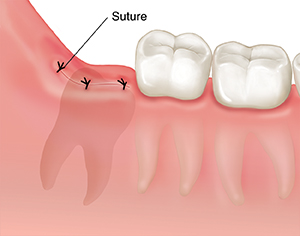

A cut (incision) may be made in the gum. This creates a flap of gum tissue that can be folded back to expose the bone and the tooth. In some cases, the surgeon may be able to loosen the tooth and remove it with forceps. The tooth may need to be cut into pieces (sectioned). Bone around the tooth may also need to be removed. In rare cases, only the crown of the tooth is removed (coronectomy). After the tooth has been removed, any incision that was made is closed with stitches.

| The wisdom tooth is removed through an incision. The incision is closed with stitches (sutures). |